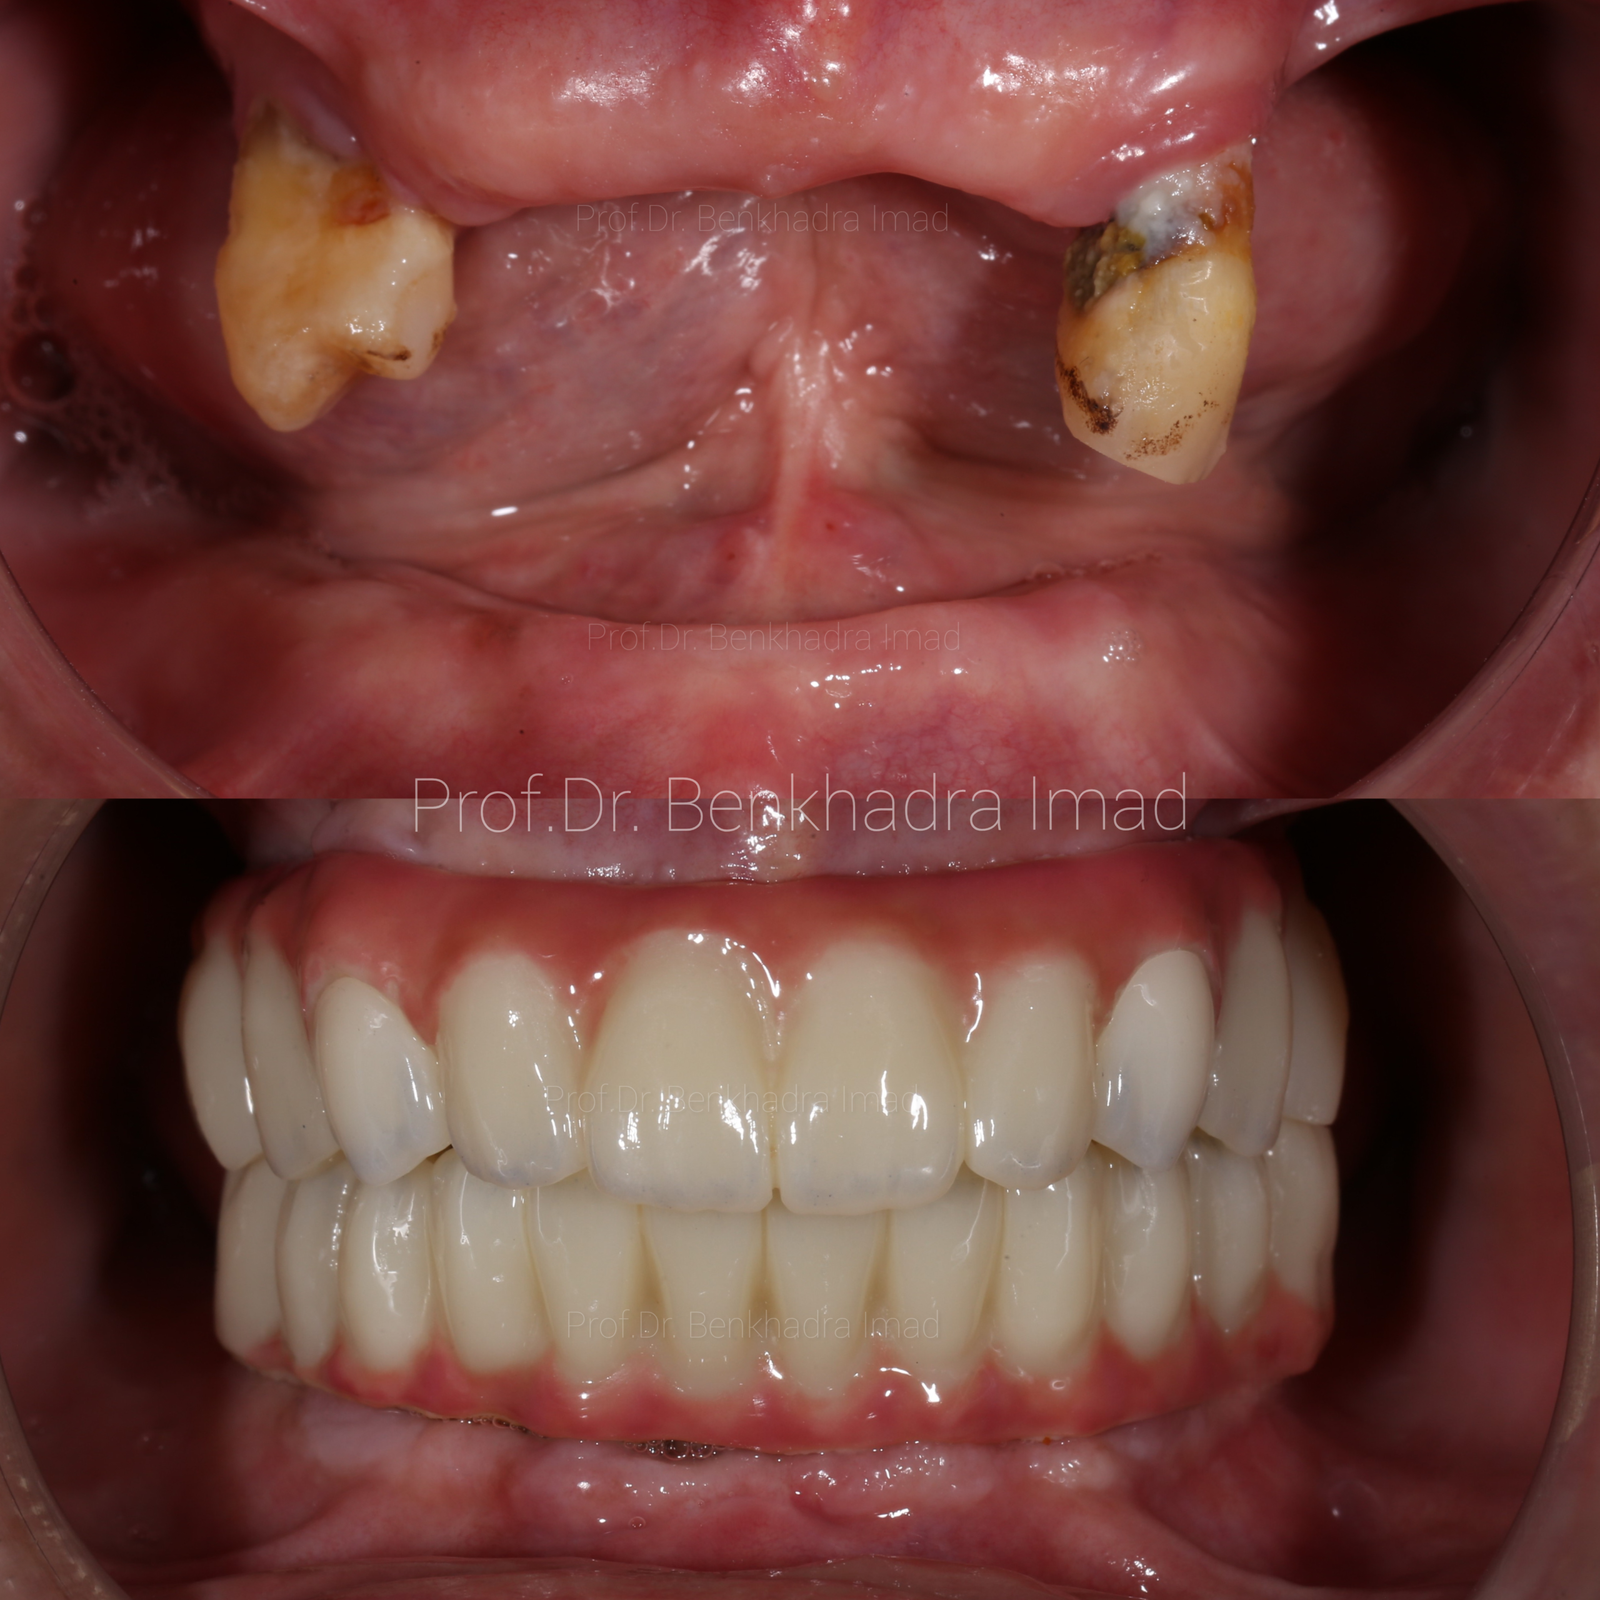

Full Smile Rehabilitation with Dental Implants | Real Case